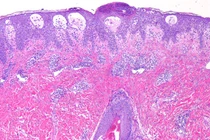

Hội chứng Stevens-Johnson và hoại tử thượng bì nhiễm độc là những phản ứng do thuốc ít gặp nhưng rất nặng, đe dọa tính mạng của người bệnh. Tần suất của bệnh trong dân số chỉ khoảng 2/1.000.000 người nhưng tỷ lệ tử vong của bệnh rất cao, tới 5-30%.